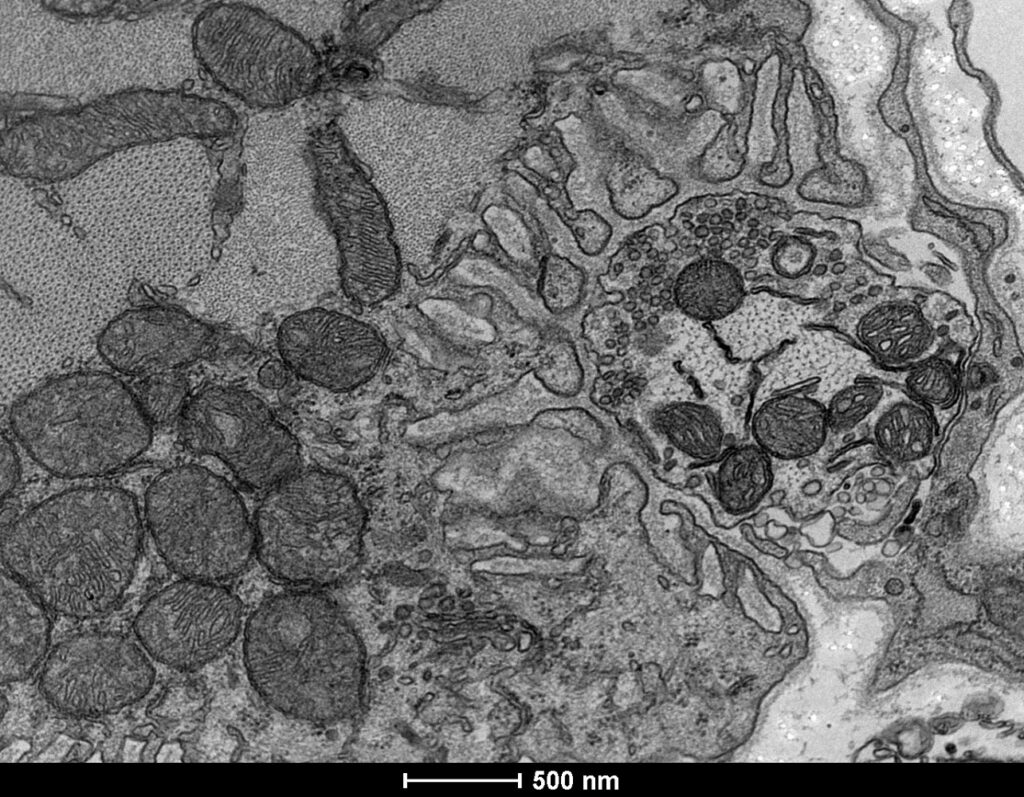

Imagem de junção neuromuscular em músculo diafragma de camundongo.

Equipamento: Microscópio Eletrônico de Transmissão Tecnai G2-12 – Spirit Biotwin FEI – 120kV

Imagem cedida por Hermann Alecsandro Rodrigues e Cristina Guatimosim Fonseca, Departamento de Morfologia, ICB, UFMG.